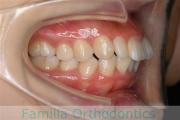

No.22V-409

- 叢生

- 16歳

- 女性

- 44

- 8|58

- FEA

- 86万円

八重歯を治したいということで来院されました。下あごの左ずれのある上顎前突(出っ歯)・叢生(でこぼこ)でしたので、上は左右から、下はで左のみ小臼歯を抜歯して、歯科矯正用アンカースクリューとマルチブラケット法にて治療を行いました。2年強、30回程度の通院が必要でした。

上下とも前歯の叢生(でこぼこ、凹凸、ガタガタ)があるため、保定を怠ると後戻りのリスクがあります。